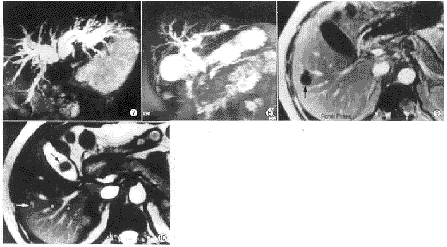

图1~3 男性,65岁。胆总管多发结石。True FISP冠状面(图1)和MRCP断面图(图2)清楚显示结石。MRCT MIP像未能显示结石 图4 男性,47岁。胆囊结石。FLASH T1WI上结石呈高信号 图5、6 男性,71岁。壶腹癌(箭头)。True FISP冠状面(图5)清楚显示胆总管扩张和软组织肿块。MRCP未能显示肿块 图7 女性,61岁。肝门胆管癌。左右肝管断端呈圆锥形 图8 女性,56岁。胰头癌。胆总管下端呈不规则鼠尾状狭窄,胆管胰管扩张 图9、10 男性,52岁。胰腺癌肝转移。FLASH T1WI动态增强门静脉期(图9)右肝转移灶清楚显示(箭头)。True FISP未能显示转移灶全貌(白箭头),胆囊区低信号影(黑箭头)为肠道气体造成的磁化率敏感伪影

2.2.2 肿瘤的显示: MRCP断层像能部分显示肿瘤形态。True FISP像可较清楚地显示肿瘤的外形轮廓、大小及侵犯范围。而在MRCP MIP像上则难于显示(图5、6)。结合以上几种成像方法,发现30例肿瘤所致的扩张胆管形态多呈“软藤”状,其近端有以下几种形式:截断性梗阻最常见,有17例(17/30,56.7%),其断端呈“截断”状或“杯口”状(图5、6);锥形或圆锥形狭窄梗阻6例(6/30,20.0%)(图7);不规则状狭窄4例(4/30,13.3%);鼠尾状狭窄梗阻3例(3/30,10.0%)(图8)。True FISP像可显示2例门脉受侵、1例十二指肠受侵征象。其他序列显示不满意。1例肝内转移灶True FISP序列显示不满意,而T1加权图像等显示良好(图9、10)。

2.2.3 其他病变的显示: 胰腺炎病例在MRCP像显示有不规则胰管扩大3例(3/5),1例合并胆管扩张,T1加权FLASH脂肪抑制像和True FISP序列对胰腺形态改变显示较好,后者对急性胰腺炎的渗出改变敏感。CT发现胰腺钙化在所有MRI序列均未显示。胰腺囊性病变3例,其中1例显示囊肿与胰管相通。MRCP对先天性总胆管扩张形态显示很好,1例疑肝Caroli's病显示胆管稍扩张,全肝均有点状高信号灶,与多囊肝难于鉴别。